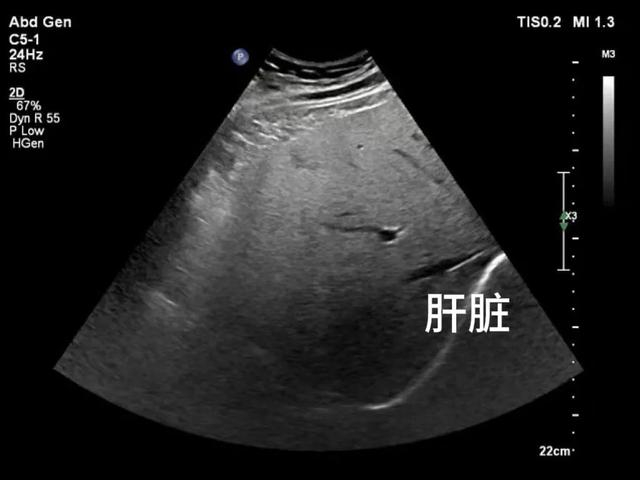

脂肪肝在超声的表现及分级

脂肪肝超声主要表现为肝脏实质明亮,呈密集弥漫的细小点状回声,肝肾对比度增加。随脂肪肝程度的增加,肝内血管显示不清,肝脏后部分回声衰减变强。

轻度脂肪肝声像图

肝脏大小、形态正常,实质回声呈密集细小,近场增强,远场衰减不明显,肝内血管、膈肌结构清晰。